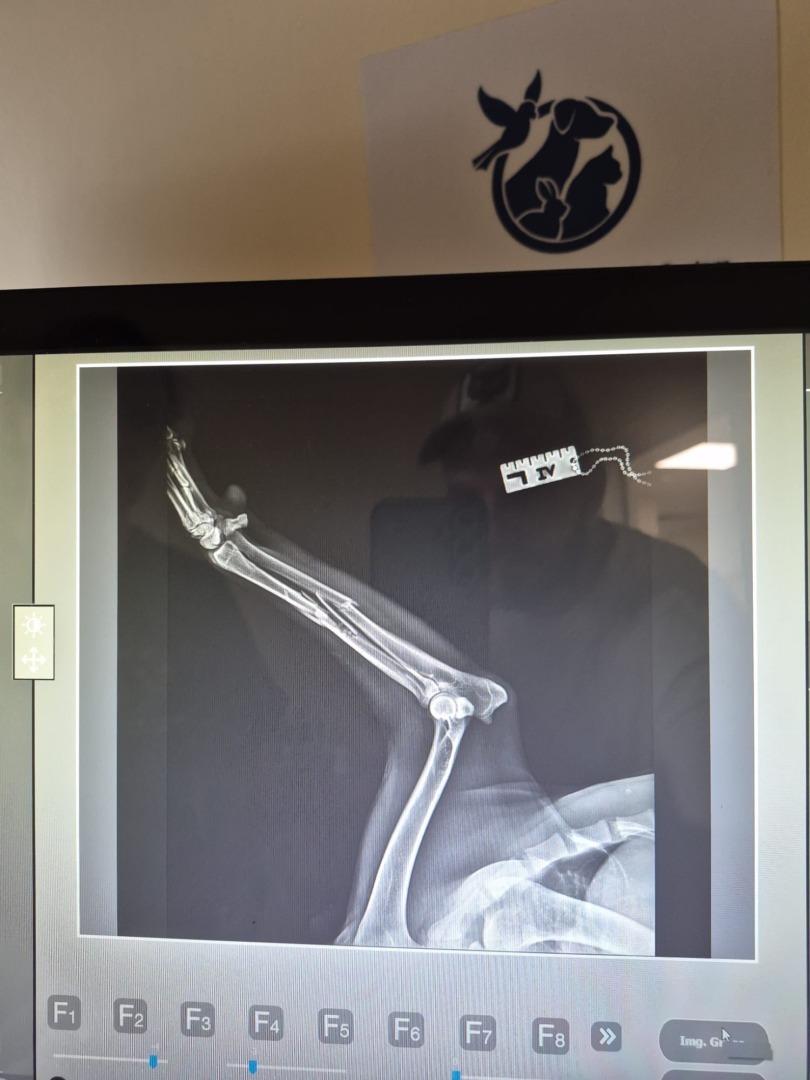

Câinele, identificat prin microcip, a fost preluat de echipa Protecției Animalelor din cadrul Consiliului Județean Ilfov. Rănit grav, cu multiple fracturi, a fost transportat de urgență la medicul veterinar Aurelian Ștefan și echipa sa, care au reușit să-i salveze viața. În prezent, malinoisul se află în regim de foster și este în afara oricărui pericol.